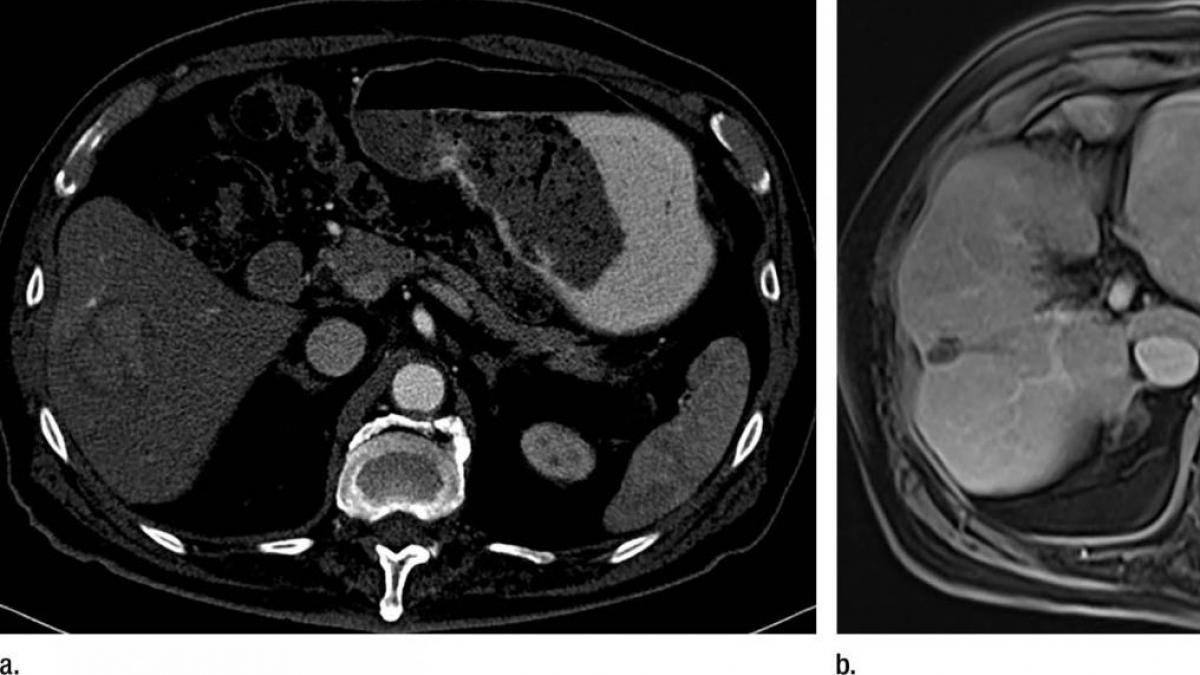

El carcinoma hepatocelular (CHC) es un tumor agresivo con opciones de tratamiento muy limitadas. Representa el 90% de todos los tumores de hígado y es diagnosticado a 6.500 personas en España cada año. Globalmente no es uno de los tipos de cáncer más frecuentes, sin embargo, como explican los expertos tiene una extrema letalidad: una tasa de supervivencia a un año de menos del 50% después del diagnóstico.